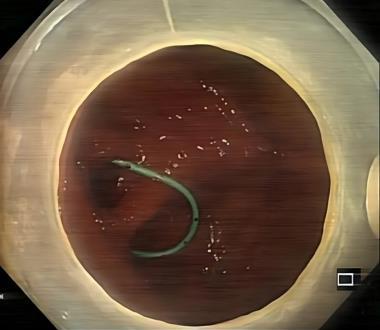

• 一次性子母胆道镜辅助内镜逆行阑尾炎治疗术对急性非复杂性阑尾炎的诊断和治疗价值分析

摘要:目的 探讨一次性子母胆道镜辅助内镜逆行阑尾炎治疗术在急性非复杂性阑尾炎治疗中的诊断和治疗价值。方法 回顾性分析2022年9月-2024年9月该院内镜中心通过一次性子母胆道镜辅助内镜逆行阑尾炎治疗术治疗的39例急性非复杂性阑尾炎患者的临床资料,观察内镜下表现、子母网篮取石率、阑尾支架置入率、技术成功率、临床成功率、手术时间、住院时间、并发症发生率和术后6 h视觉模拟评分法(VAS)评分,以及术后24 h炎症指标。结果 28例(71.8%)患者结肠镜下阑尾开口可见充血和水肿,10例(25.6%)患者结肠镜下阑尾开口可见脓液流出,32例(82.1%)患者子镜下阑尾腔内可见大量脓液,20例(51.3%)患者子镜下阑尾腔内可见粪石;一次性子母胆道镜辅助内镜逆行阑尾炎治疗术的技术成功率为100.0%(39/39);手术时间(21.08±7.49)min;住院时间(3.97±2.08)d;8例(20.5%)患者行内镜下子母网篮取石术;14例(35.9%)患者行阑尾支架置入术。临床成功率为97.4%(38/39),1例患者术后临床症状和炎症指标未缓解,转外科行阑尾切除术。38例患者术后6 h的VAS评分 < 3分,腹痛症状明显缓解;术后24 h白细胞计数和中性粒细胞百分比较术前明显下降,差异均有统计学意义(P < 0.05);39例患者均未发生并发症;术后随访(5.94±4.03)个月,3例(7.7%)出现复发。结论 一次性子母胆道镜辅助内镜逆行阑尾炎治疗术诊断和治疗急性非复杂性阑尾炎,安全且有效,值得临床推广应用。